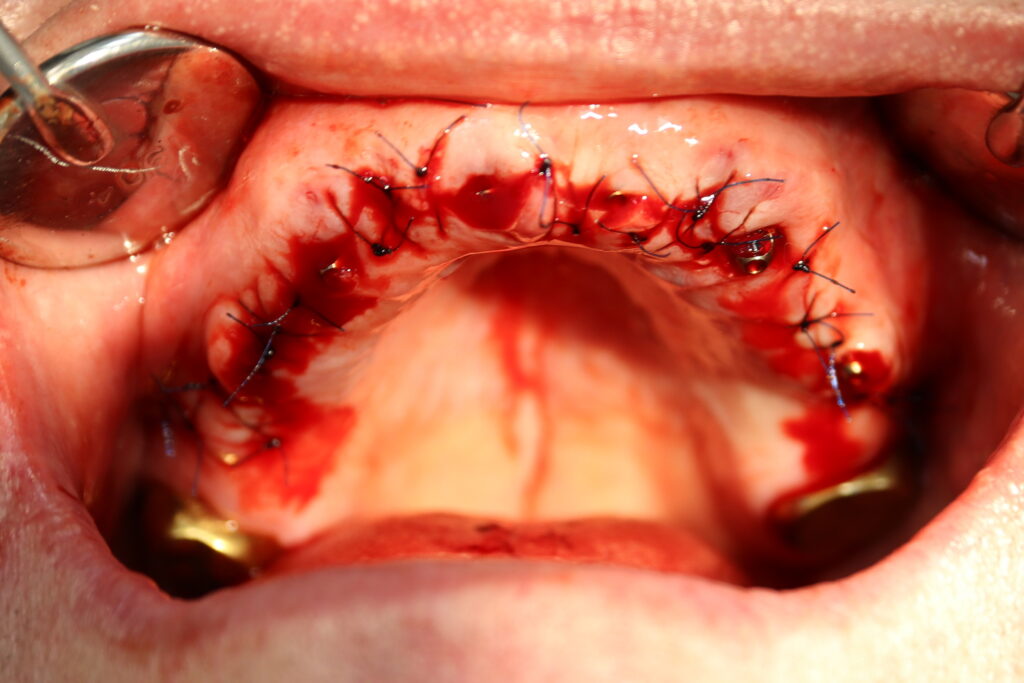

процесс имплантации

Это фото может содержать тяжелый для восприятия контент

Пациенту были установлены 6 имплантатов Megagen AnyOne по системе All-on-6 на верхней челюсти и 4 имплантата на нижней по классической двухэтапной методике.